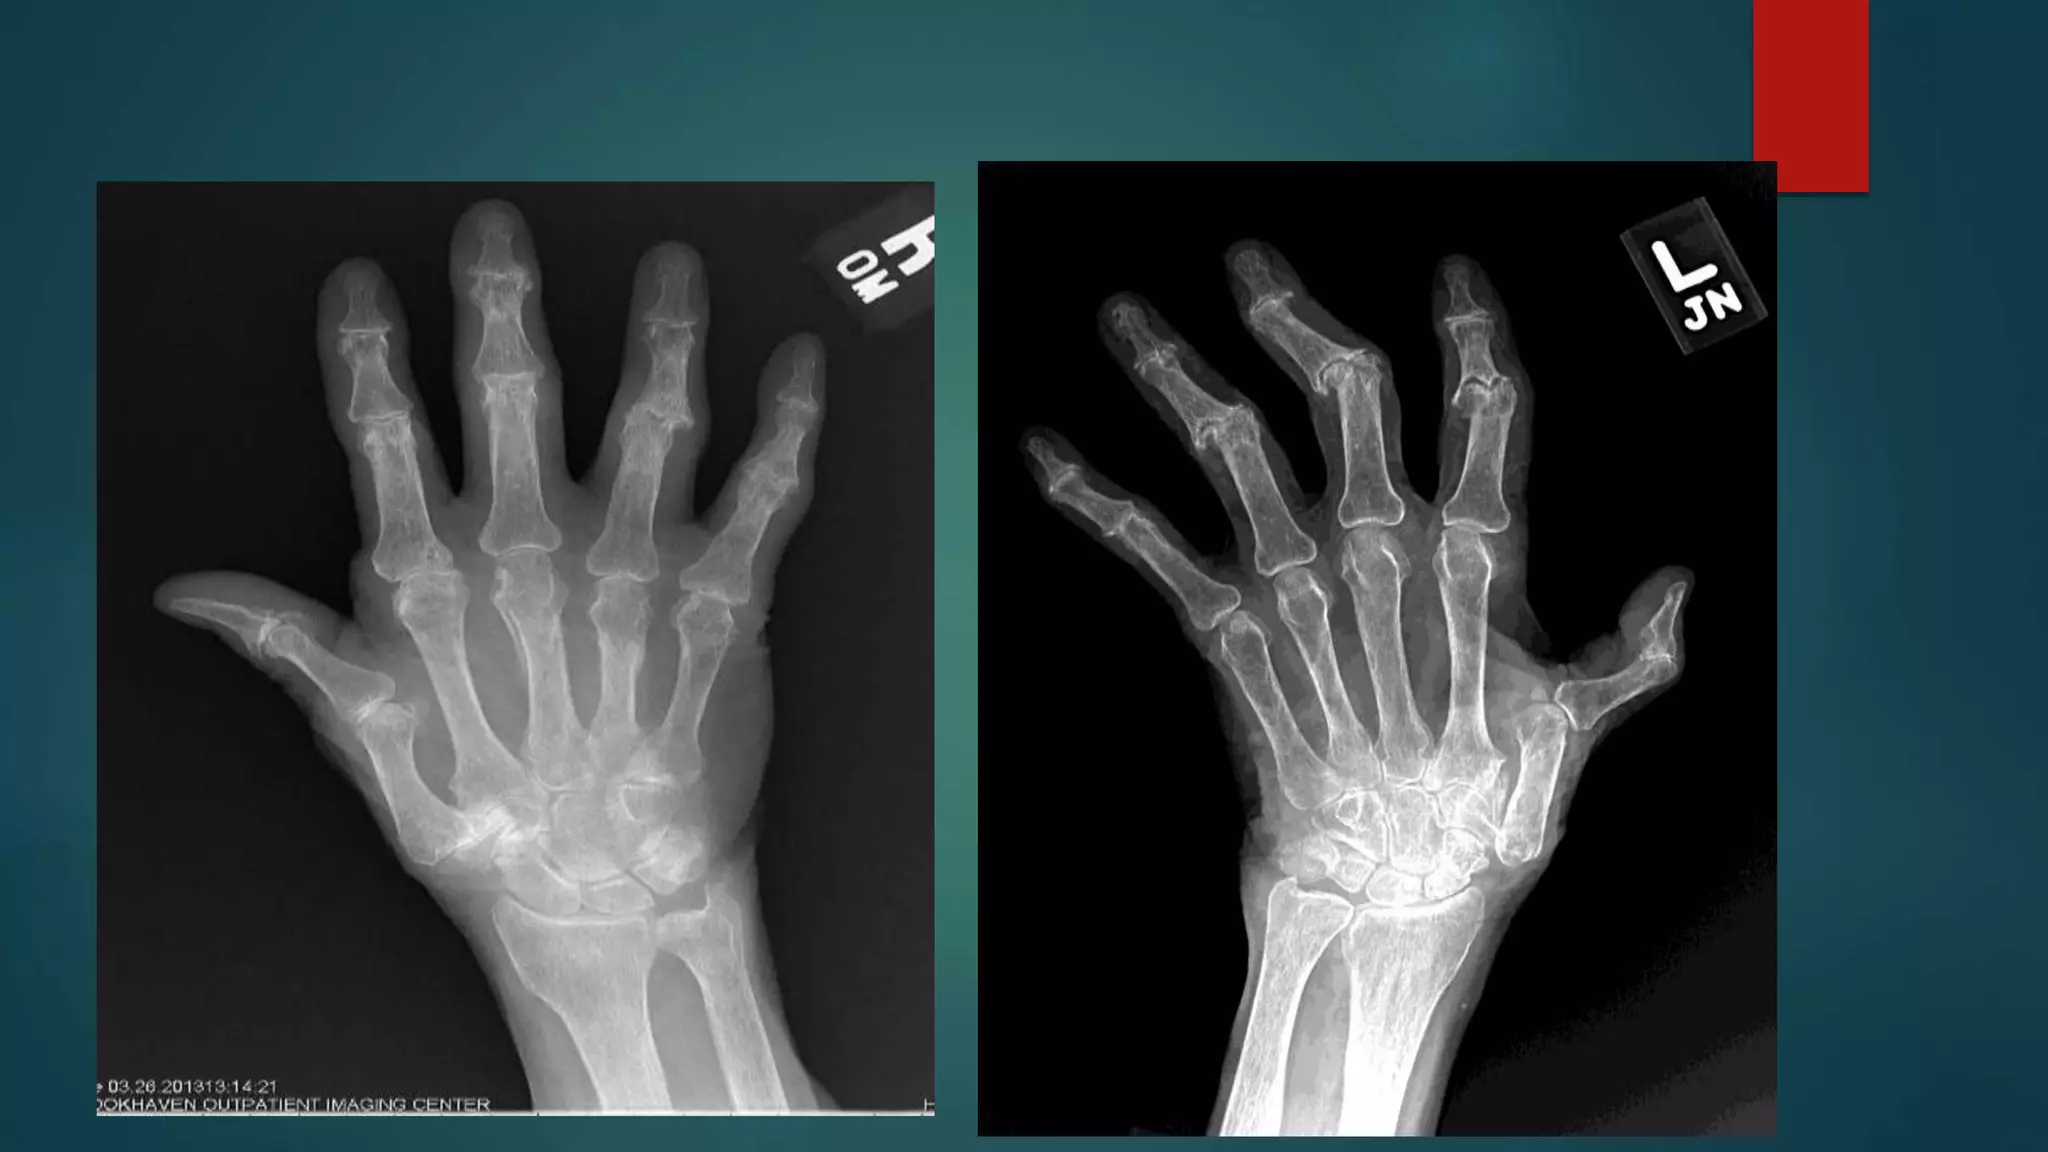

EROSIVE

 Erosive osteoarthritis has a predilection for the hands. The

dominant features are those of osteoarthritis, particularly in

terms of distribution:

• distal interphalangeal (DIP) joints

• proximal interphalangeal (PIP) joints

• first carpometacarpal (CMC) joint

 Additional characteristic features include:

• diffuse cartilage loss, with joint space narrowing

• subchondral erosions (at least two central erosions affecting

separate interphalangeal joints); typical central location of the

erosions produces the classic "gull-wing" appearance

• joint ankylosis

• absence of 2

• marginal erosions

• fusiform soft-tissue swelling

• osteopenia

RA

• #80 1. Severe joint space narrowing at the first carpometacarpal joint and the interphalangeal joints. At the first carpometacarpal joint there is associated subchondral sclerosis and cyst formation. There are also subchondral central erosions at the heads of the proximal phalanges with marginal osteophytes involving the distal phalangeal bases, demonstrating gull wing deformity through the second and fifth digits. Severe joint space narrowing, subchondral sclerosis, and erosive changes of the scaphoid-trapezium and scaphoid-trapezoid joints. Narrowing of the radiocarpal joint. Diffuse osteopenia. Findings are keeping with erosive osteoarthritic changes 2. Extensive erosive changes and alignment abnormalities are observed along the articular surfaces of the 2nd through 5th PIP and DIP joints bilaterally, as well as at the 1st IP, MCP and carpometacarpal joints bilaterally. These erosive changes assume a gull wing appearance. The alignment abnormalities involving the 1st digits resemble a hitchhiker's thumb. There are no significant erosive changes involving the radiocarpal or intercapral joints, and the 2nd-5th MCP joints are also spared.